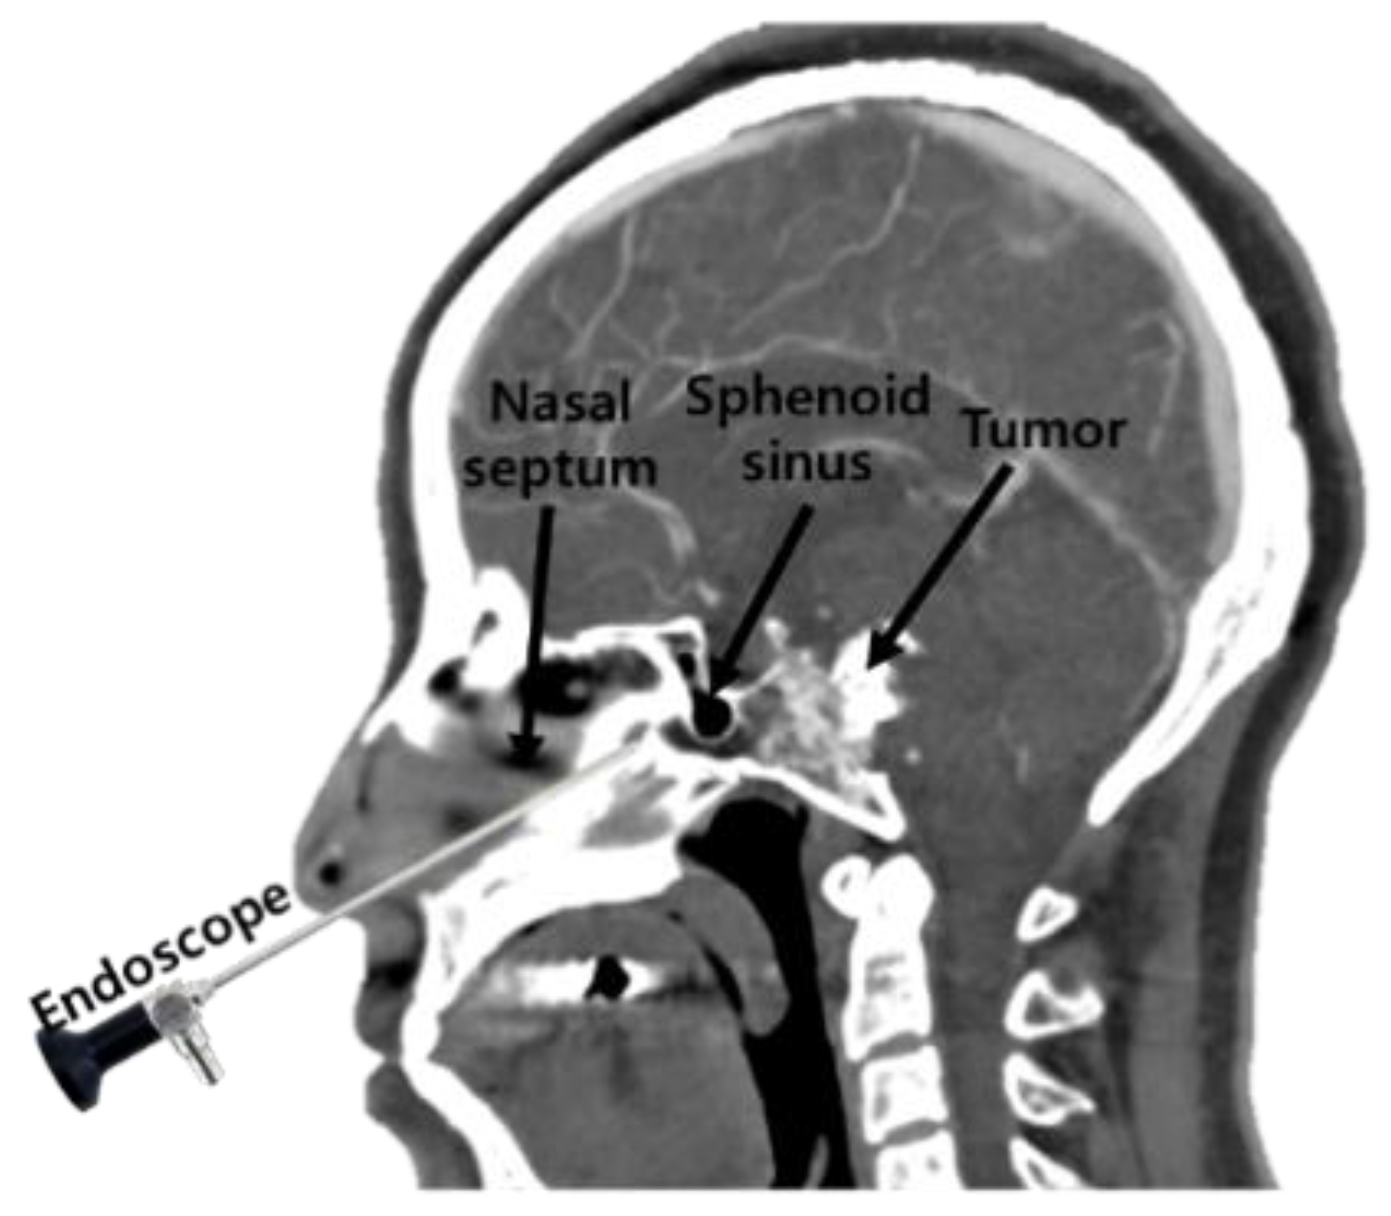

3.1. Proposed Surgical Navigation System